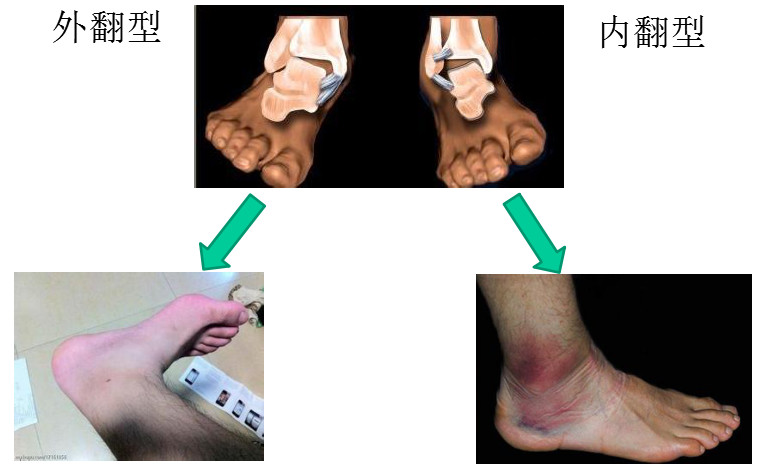

崴脚就是医学上说的踝关节扭伤,是由于足部受力不均,踝关节过度向内或向外翻,导致的踝关节损伤。

踝关节扭伤是最高发、最常见的运动损伤,约占所有运动损伤的40%。其中80%伴有韧带损伤。

(2)接着局部红肿、温度升高,继出现青紫瘀斑,局部压痛明显。